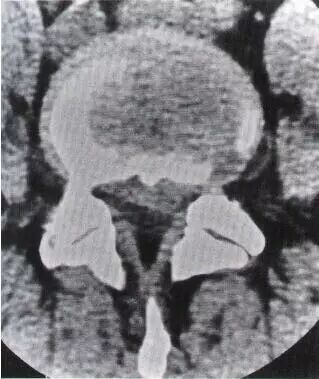

脊柱腰段解剖图